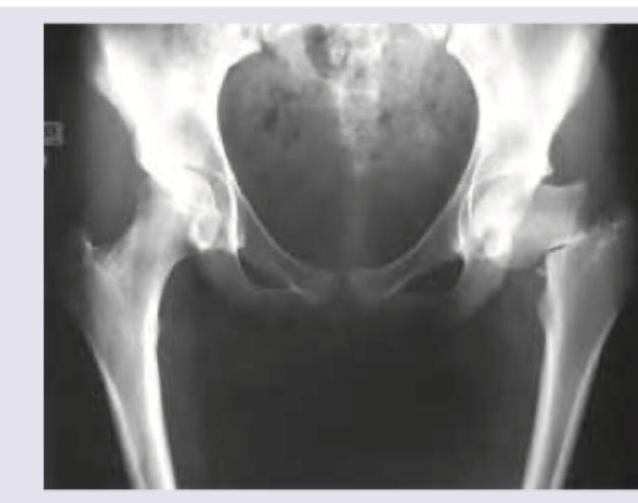

Question 7: What is the grade of fracture according to Garden's classification?

- A. Grade I

- B. Grade II

- C. Grade III (Correct Answer)

- D. Grade IV

Explanation: ***Grade III*** - This image shows a **complete displaced fracture** of the femoral neck, but with the **distal fragment in valgus** position, which corresponds to Garden Grade III. - In Garden Grade III, the fracture is **complete and displaced**, but there is still some **engagement** of the fracture surfaces, leading to the valgus alignment of the head on the shaft. *Grade I* - Garden Grade I refers to an **incomplete impacted valgus fracture** of the femoral neck. - The fracture line is visible, but there is no displacement, and the head is tilted into a valgus position relative to the neck. *Grade II* - Garden Grade II describes a **complete but non-displaced fracture** of the femoral neck. - The fracture line extends across the entire neck, but the fragments remain in anatomical alignment without angulation or displacement. *Grade IV* - Garden Grade IV is characterized by a **complete and fully displaced fracture** of the femoral neck, with the **femoral head completely separated** from the shaft and in a neutral or varus position. - There is a complete loss of contact and alignment between the femoral head and the shaft, indicating significant instability.